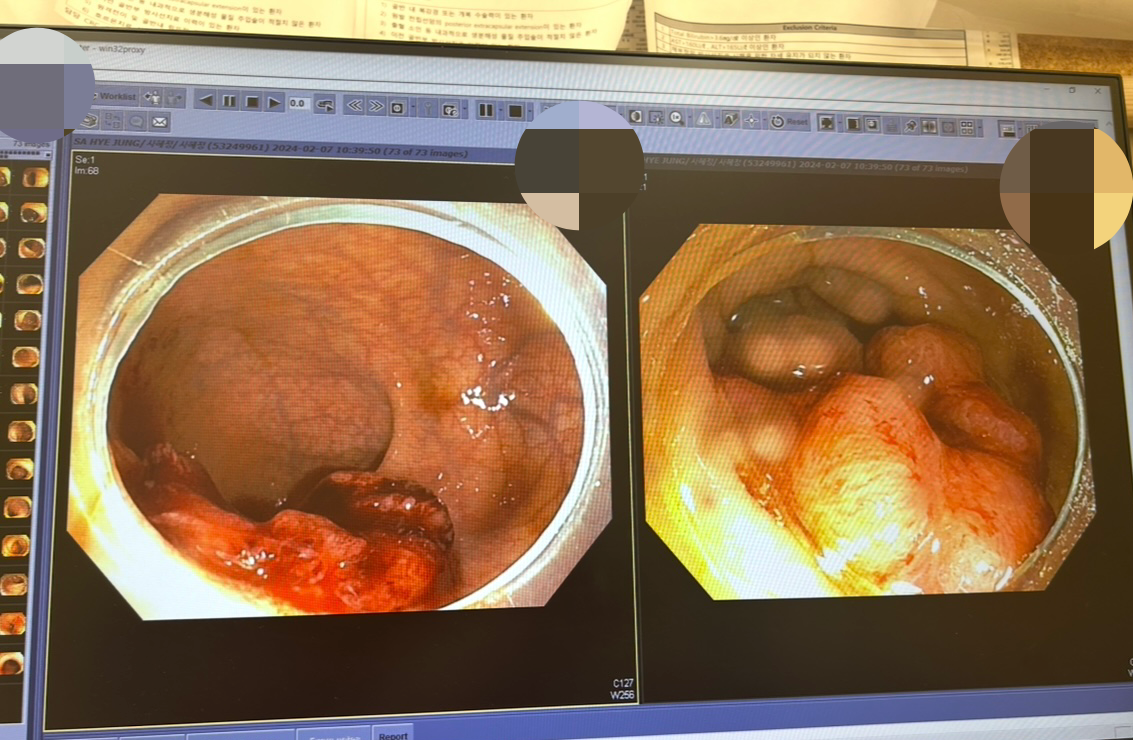

2024.2.7 직장암 진단 시 : +++ 내과

-왼쪽은 조직 검사 후

2024.5.16 : 000 내과

-암은 사라지고 붉은 흔적만 남아 있다.